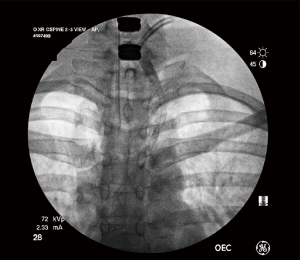

The tracheoesophageal complex was investigated, and no breach was determined. However, the patient had some air coming from the inferior aspect of the wound that was cyclical with the anesthesia ventilations. There was not a distinct link seen in this area. Valsalva was applied and there was no problem with the tracheoesophageal area. An upright fluoroscopic chest X-ray (CXR) was obtained and there was no pneumothorax identified in the operating room as determined with c-arm intensification (Figure 3).

Figure 3 Anterior-posterior view of cervical spine and chest during operation; not demonstrating pneumothorax. The patient has the head of the bed elevated at 30 degrees.